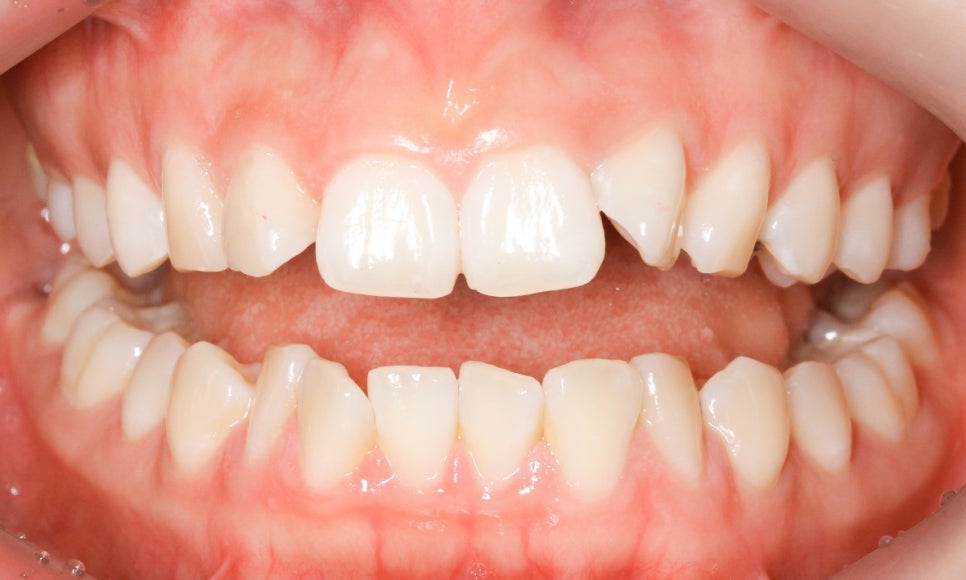

다음으로 상하악의 교합부를 보시면

상악과 하악이 교합되는 부위가

전치부 crowding으로 인해 약간

삐뚤거리는 모습을 확인할 수 있는데요,

특히 앞니틀어짐 있는 22번 측절치로 인해

전치부의 교합이 바르지 못한 모습입니다.